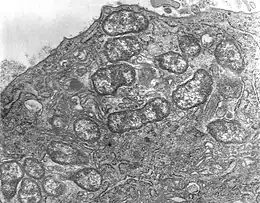

Orientia tsutsugamushi, unique représentant du genre Orientia, est une espèce de bactéries responsables de la fièvre fluviale du Japon.